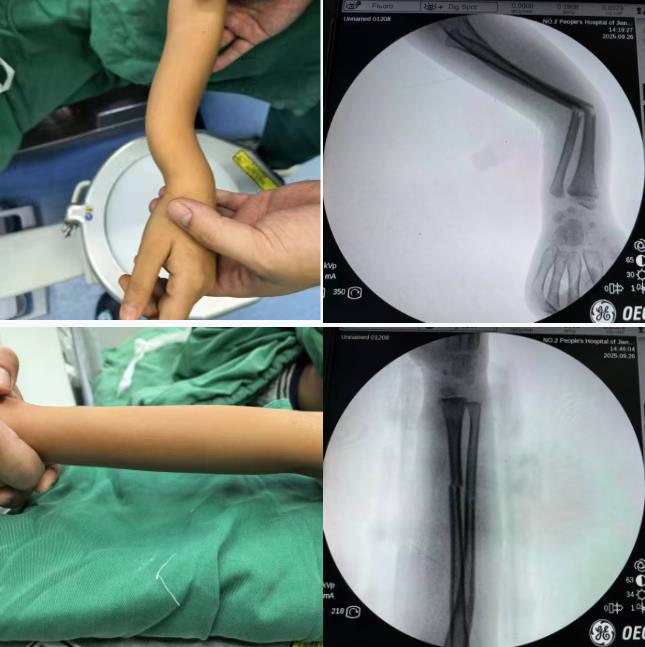

精准复位是前提:麻醉成功后,潘月帆主任及李林鹏医师实施正骨手法,拔伸牵引、折顶端提、挤压分骨、摇摆触碰……通过正骨手法纠正骨折端移位,最大程度保证骨折良好的对位对线,为骨折的愈合和功能恢复打下基础。

个性化固定是关键:采用夹板加压垫固定,防旋中立位板制动,有效维持复位;压垫纠正残余错位、帮助维持复位、减轻皮肤受压,提升舒适度。

潘月帆主任和李林鹏医师在为王先生行夹板外固定。

一例儿童尺桡骨双骨折应用手法正骨治疗的病例。